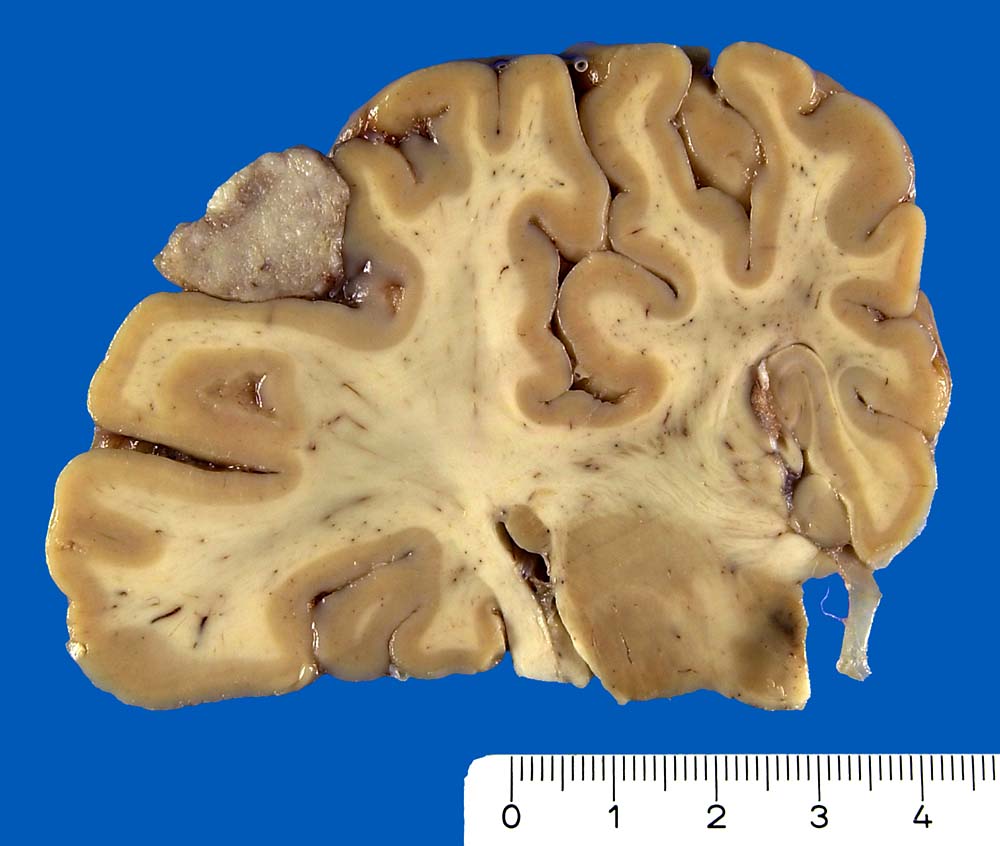

PathoPic ID 8844 - Meningotheliomatöses Meningeom (WHO Grad I)

Meningotheliomatöses Meningeom (WHO Grad I)

Der parietalen Hirnrinde anliegender kugeliger grauer Tumorknoten.

Makroskopie